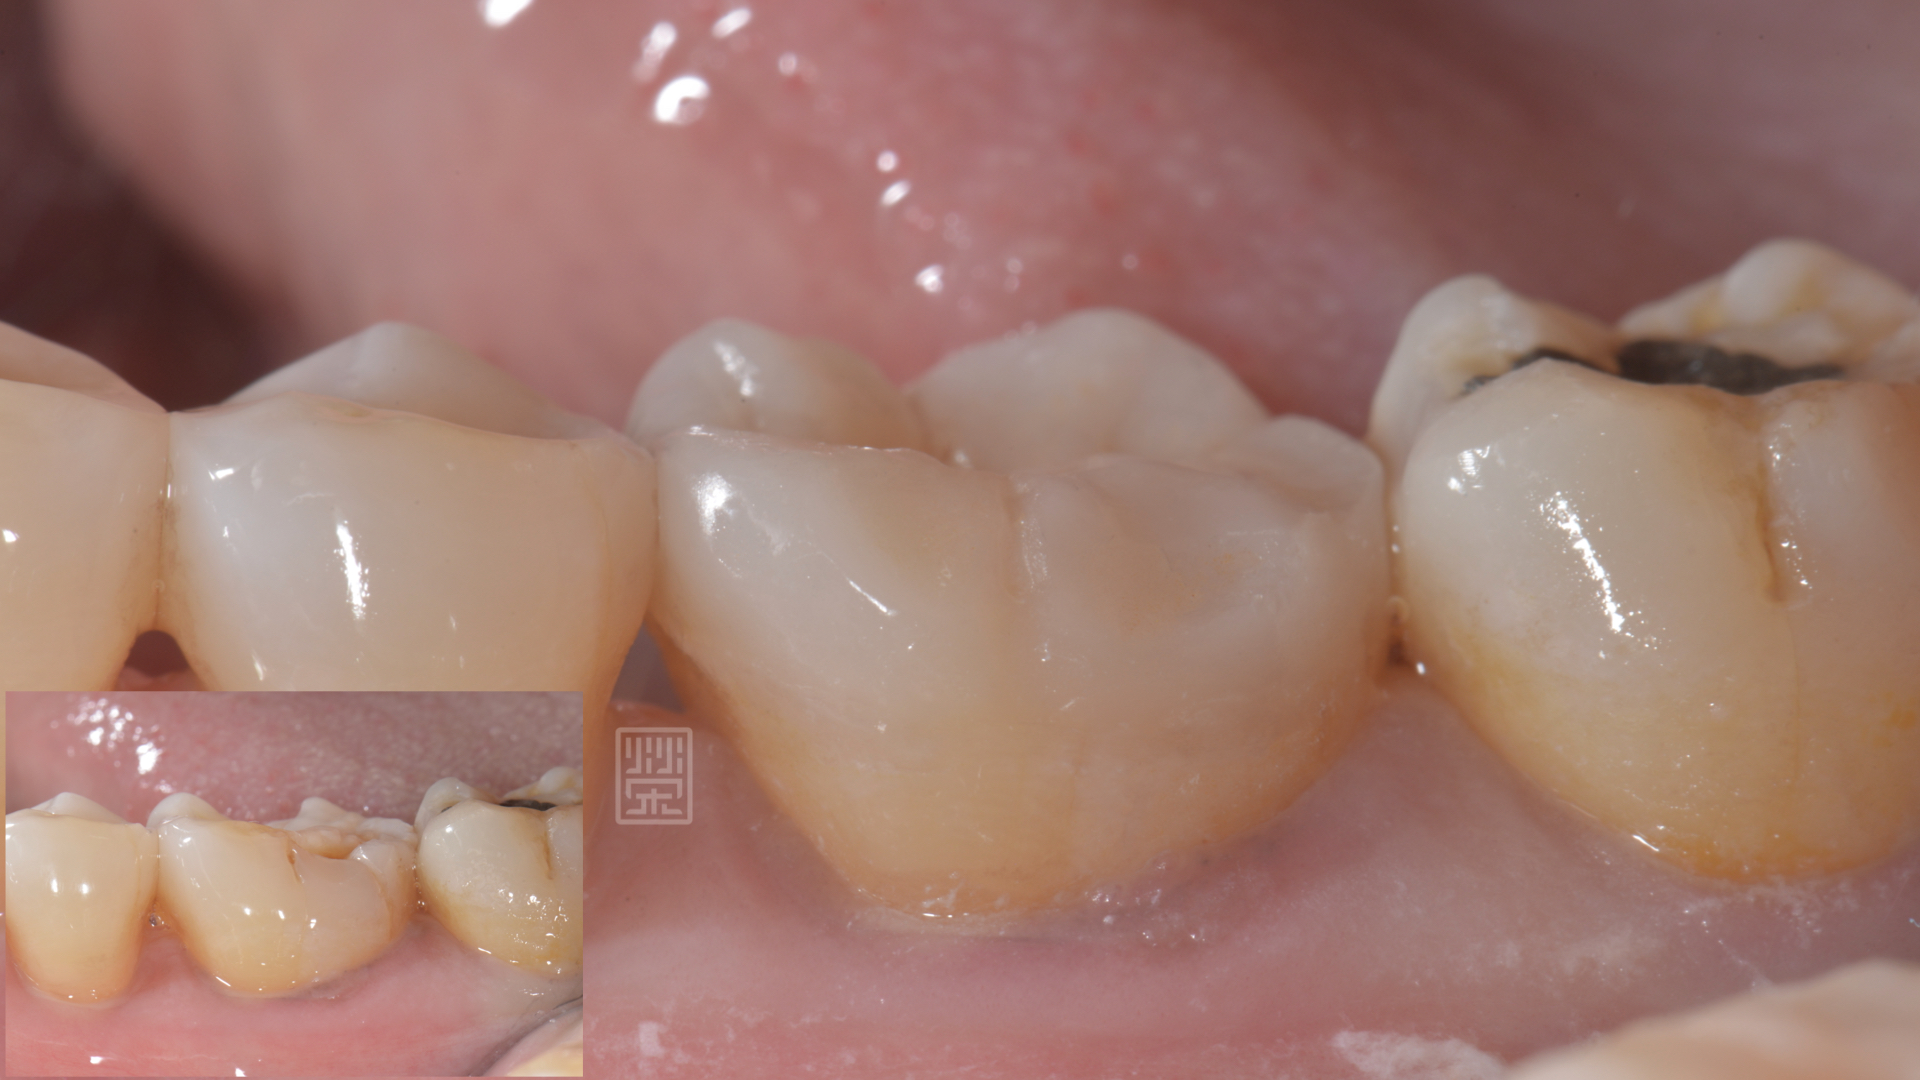

楊女士因為上顎第二大臼齒缺牙,所以咬合重心都是在第一大臼齒咬合對,前陣子突然發覺咬東西有點痛痛的,以為是牙齦發炎,認真刷牙後,狀況並未改善,來榮醫師診間就診,發現除了咬合面明顯磨耗,牙本質都裸露之外,頰側面有明顯的縱向裂痕,還好的是牙齒神經並未造成不可逆傷害,建議製作全瓷嵌體,將牙齒戴上保護罩,減少治療過程牙齒的傷害。

牙齒修磨